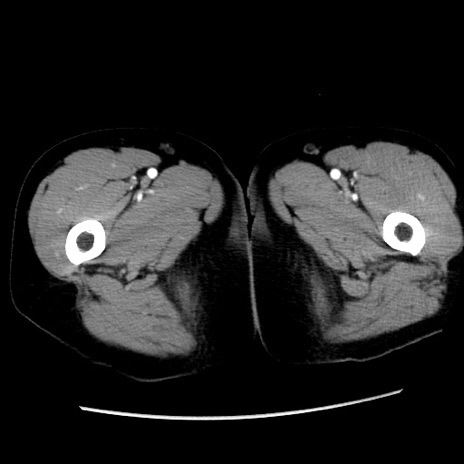

症例10(横断像)

【症例】 50歳代女性

【主訴】 腹痛

【現病歴】前日生レバーを食べた。今朝に排便あり。 昼前に突然発症の腹痛を生じ、当院救急外来を受診した。

【既往歴】 子宮筋腫にてで子宮全摘後

【身体所見】 意識清明、腹部:平坦、軟、下腹部やや左を中心に圧痛・反跳痛あり、筋性防御あり

【データ】WBC 7800、CRP 0.07